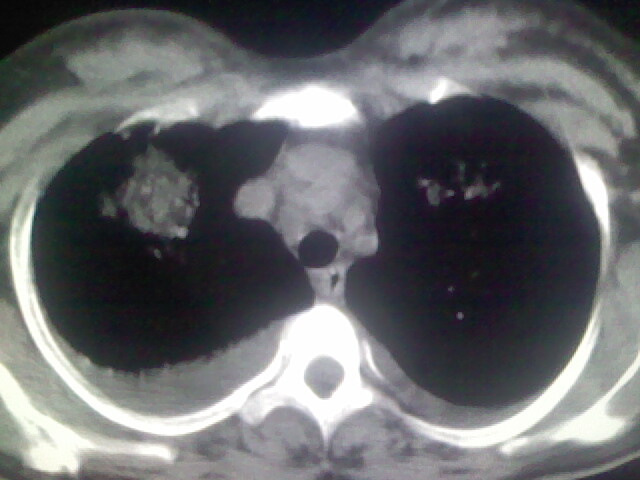

考虑肺梗塞、肺水肿,双侧胸腔积液

肝脾大,双侧胸腔积液,双肺水肿,肺动脉[包括远端小动脉],左右心房,左心室增宽,右心室主动脉无明显改变,符合左心功能不全征;;建议除外二尖瓣关闭不全,扩张性心肌病

临床资料及影象表现支持围产期扩张型心肌病改变,心衰。

考虑产后心肌病,心功能不全,肺水肿,双侧胸腔积液。

考虑产后心肌病,心功能不全,肺水肿,双侧胸腔积液。不排除羊水栓塞可能。